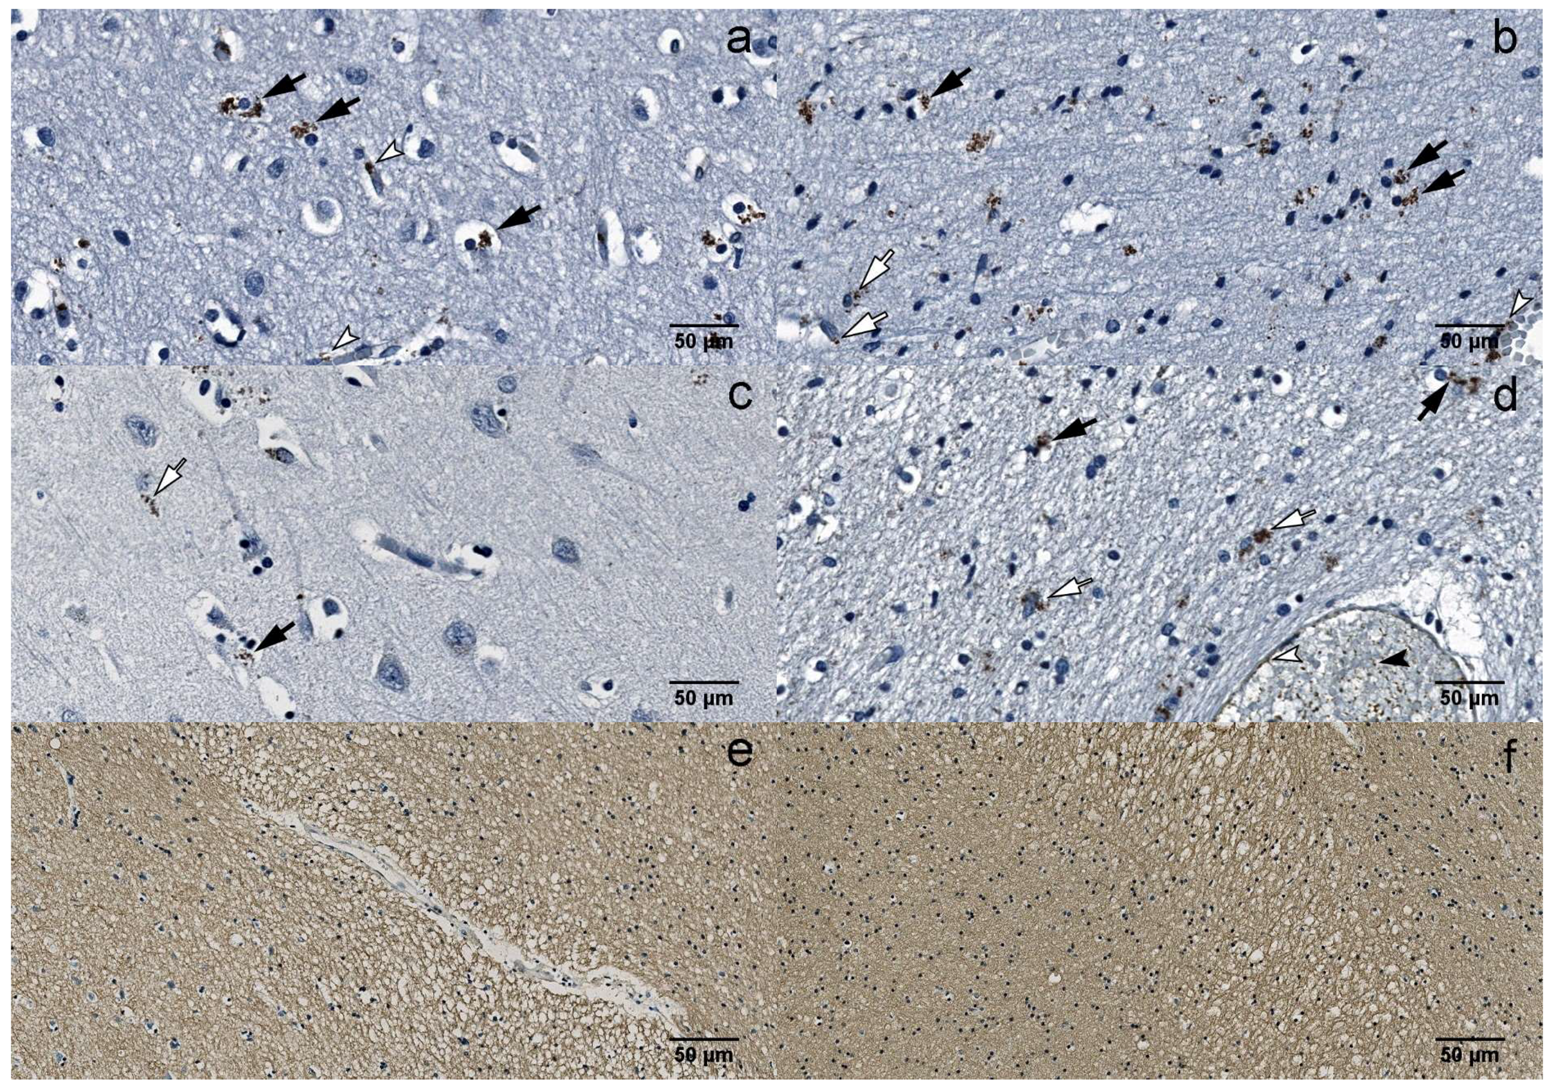

Figure 3. IHC: (a) B19V-positive oligodendrocytes (black arrows) and endotheliocytes (white arrowheads) in the gray matter of the UEP subject (frontal lobe, 400×); (b) B19V-positive oligodendrocytes (black arrows), astrocytes (white arrows) and endotheliocyte (white arrowhead) in the white matter of the UEP subject (frontal lobe, 400×); (c) B19V-positive oligodendrocyte (black arrow) and astrocyte (white arrow) in the gray matter of the UEP subject (temporal lobe, 400×); (d) B19V-positive oligodendrocytes (black arrows), astrocytes (white arrows), endotheliocytes (white arrowhead) and erythrocytes (black arrowhead) in the white matter of the UEP subject (temporal lobe, 400×); (e) myelin basic protein (MBP) immunoexpression in the white matter of the UEP subject (frontal lobe, 400×); (f) MBP immunoexpression in the white matter of the UEP subject (temporal lobe, 400×).

There were significantly (p < 0.0001) more B19V-positive astrocytes in the white and gray matter of the frontal lobe (177 and 147, respectively) compared to the temporal lobe (68 and 64, respectively) in the UEP group (Figure 2e and Figure 3a–d). Similar observations were made in the control group (p = 0.0061 and p < 0.0001, respectively). There were significantly (p < 0.0001) more B19V-positive oligodendrocytes in the white and the gray matter of the frontal lobe (387 and 267, respectively) when compared to the temporal lobe (192 and 128, respectively) in the UEP group (Figure 2f and Figure 3a–d). In the control group, similar observations were made only in the gray matter of the frontal lobe (206 and 139, p = 0.0061).

Multiple demyelinating lesions were detected in the white matter of the UEP group (Figure 3e,f).